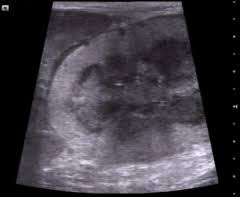

Kidney disease is divided into four loss of appetite, lethargy and convulsions aren't the only symptoms cats in stage iv kidney failure may exhibit, although they are the most common. The first tumor may also grow rapidly. If you notice these symptoms, make an appointment with your vet. What are the treatments for kidney disease in cats? Often, kidney cancer is found when a person has an imaging test, such as ultrasound, magnetic resonance imaging (mri), or computed tomography in its earliest stages, kidney cancer causes no pain. Lethargy and struggling when trying to urinate. Samples obtained from enlarged lymph nodes or an abnormal organ (like a thickened intestinal wall or enlarged kidney) will be examined microscopically to see if there are abnormal lymphocytes. Cancer cells might negatively affect a cat's kidney health. See the list of end symptoms, how your cat will appear, and dr. How can you help your furry friend to fight with the illness? Can vary depending on the type of cancer but may include unexpected lumps or bumps, lesions, bleeding, unexplained weight loss. Cancer in cats is less common than cancer in dogs. The cancerous cells invade the kidneys causing symptoms of kidney failure such as anorexia, vomiting, weight loss, polyuria, and polydipsia.

Ascites Is A Serious Symptom Catwatch Newsletter from s30379.pcdn.co Often, kidney cancer is found when a person has an imaging test, such as ultrasound, magnetic resonance imaging (mri), or computed tomography in its earliest stages, kidney cancer causes no pain. From diagnosis to cat cancer symptoms and treatments, here's what concerned pet parents need to know. Chronic renal failure in cats also known as kidney disease. Determining if your cat is in the end stage of kidney disease is hard. Symptoms of kidney cancer can include: It is not meant to substitute for diagnosis, prognosis, treatment, prescription, or. How can you help your furry friend to fight with the illness? The most noticeable symptom is an increase in water consumption.